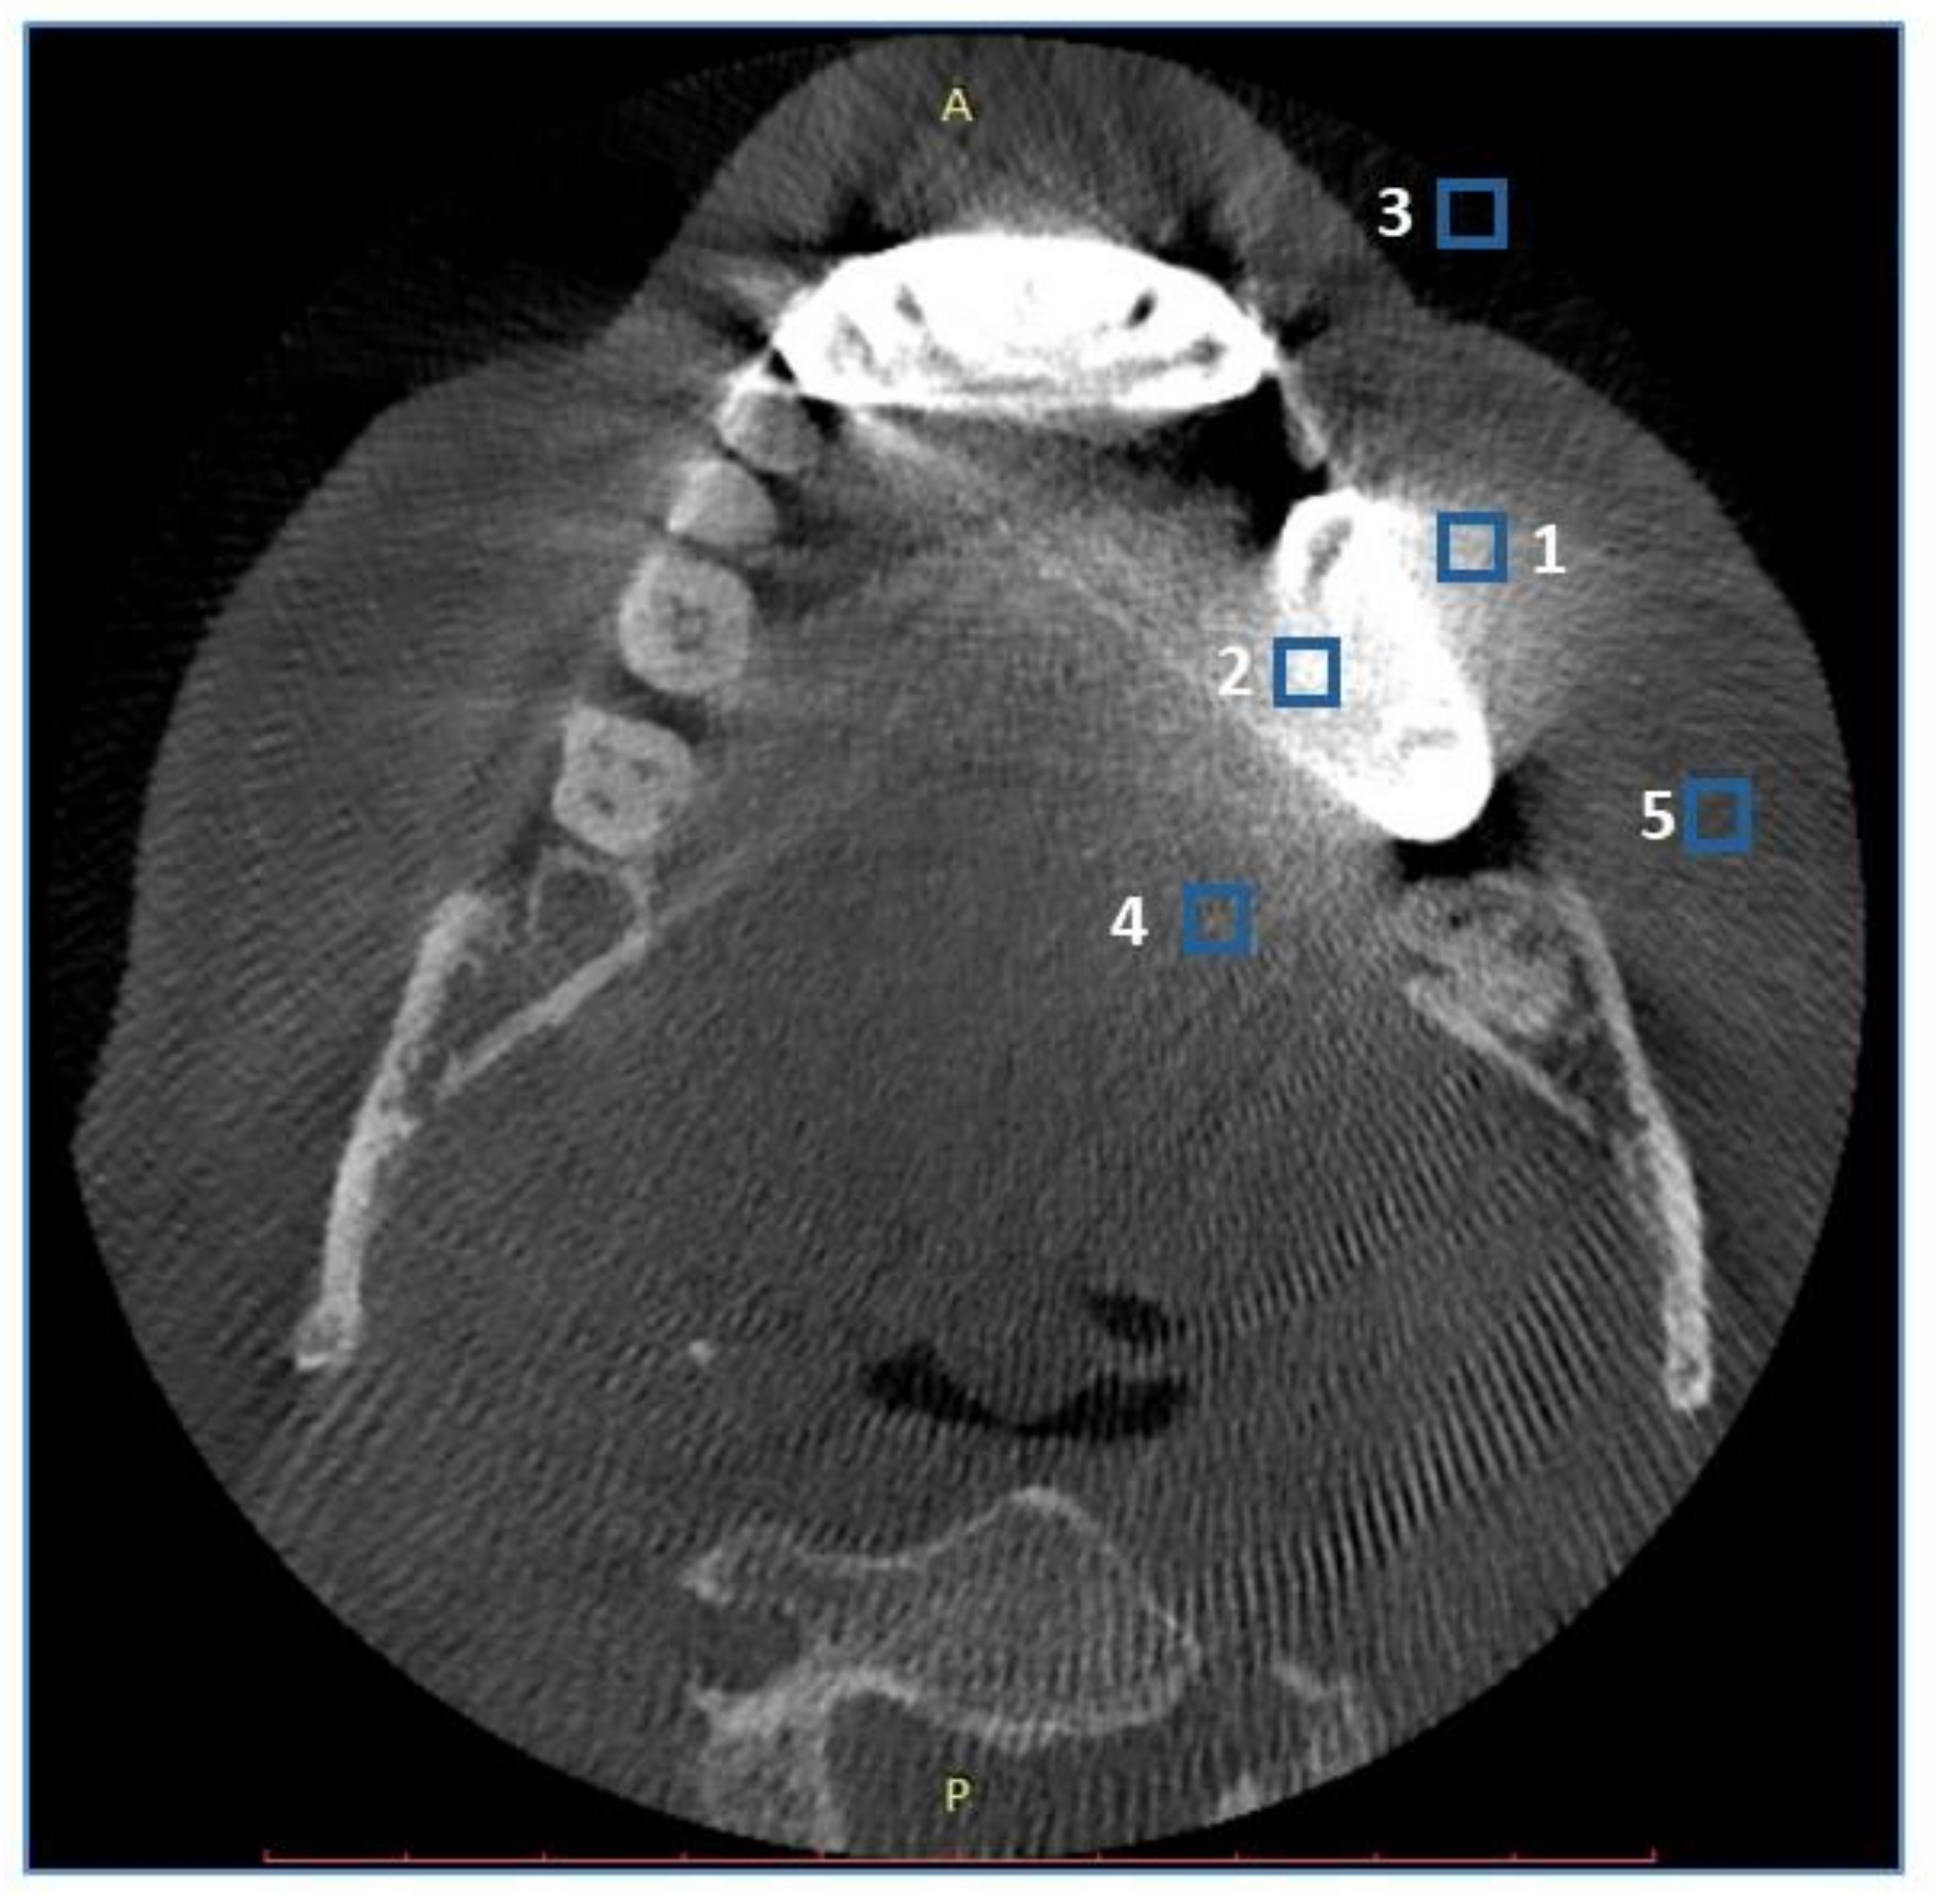

2.3. Objective Image Quality Assessment

2.4. Subjective Image Quality Assessment